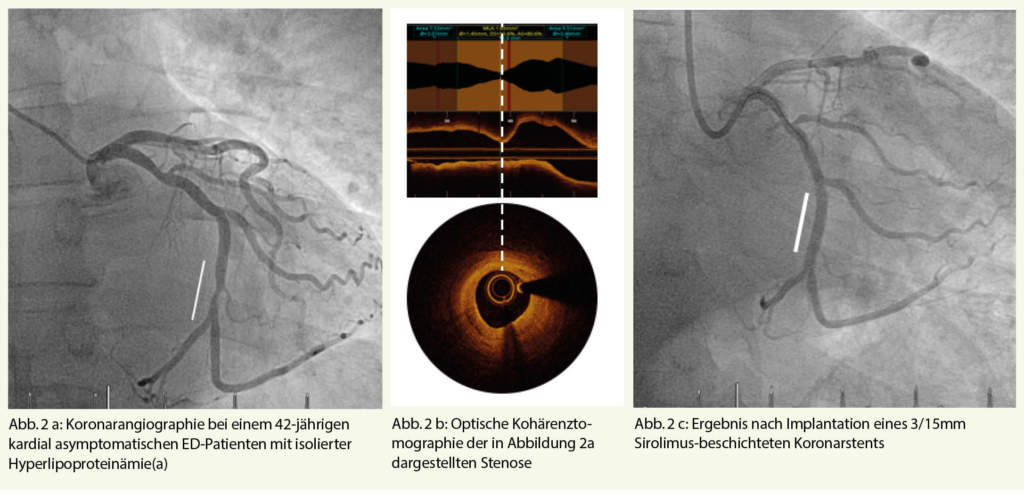

Sobald die Diagnose einer arteriell bedingten ED gesichert ist, empfiehlt sich ein fachärztliches Workup. Häufig finden sich bei Patienten mit arteriell bedingter ED auch Pathologien in anderen arteriellen Stromgebieten (Abb. 1, 2).

Die ZEN Studie beschäftigte sich mit der klinischen Effizienz der Implantation Medikamenten-beschichteter Koronarstents in Pudenda Obstruktionen (11). Die Obstruktionen waren fokaler Natur (durchschnittliche Läsionslänge 18 mm), der durchschnittliche Gefässdurchmesser betrug 2,6 mm. In allen Fällen wurde ein technischer Angioplastie- bzw. Stent-Erfolg verzeichnet, wobei sich im Nachgang herausstellte, dass bei 5 von 30 Patienten aus Versehen nicht erektions-bezogene-Arterien gestentet wurden, was die anatomische Komplexität dieser Eingriffe unterstreicht. Im Rahmen neuerer Untersuchungen zeigte eine Arbeitsgruppe, dass selbst die technisch nicht triviale Angioplastie in Händen erfahrener Interventionalisten sicher ist (14).

Eine detaillierte Studie von uns zeigte, dass die endovaskuläre Behandlung mit atherosklerotischer ED sicher und wirksam war. Der Erfolg wurde bei 49 (98%) von 50 Patienten erzielt. Nach 12 Monaten erreichten 65% der Patienten eine Verbesserung nach IIEF-6-Scores und die Veränderung des Scores war konsistent (15). So lange es noch keine randomisierten Studien gibt, sollte die Stentbehandlung für ED Patienten reserviert sein, die nicht auf konservative Therapiemassnahmen (PDE-5-Hemmer oder intrakavernöses Prostaglandin) ansprechen. Abbildung 4 zeigt eine komplexe Intervention bei einem 66-jährigen ED-Patienten mit Stenose der Penisarterien-Bifurkation. In koronarer Bifurkations-Technik wird der Abgang der A. cavernosa zunächst mit einem Sirolimus-beschichteten Stent überstentet (Abb. 4b) um den Fluss in die für die Rigidität der Eichel wichtige A. dorsalis penis zu gewährleisten. Im Anschluss wird die für die Rigidität des proximalen Penisschaftes wichtige A. cavernosa mit einem Draht sondiert und mit einem weiteren beschichteten Stent durch die Maschen hindurch gestentet (Abb. 4c).